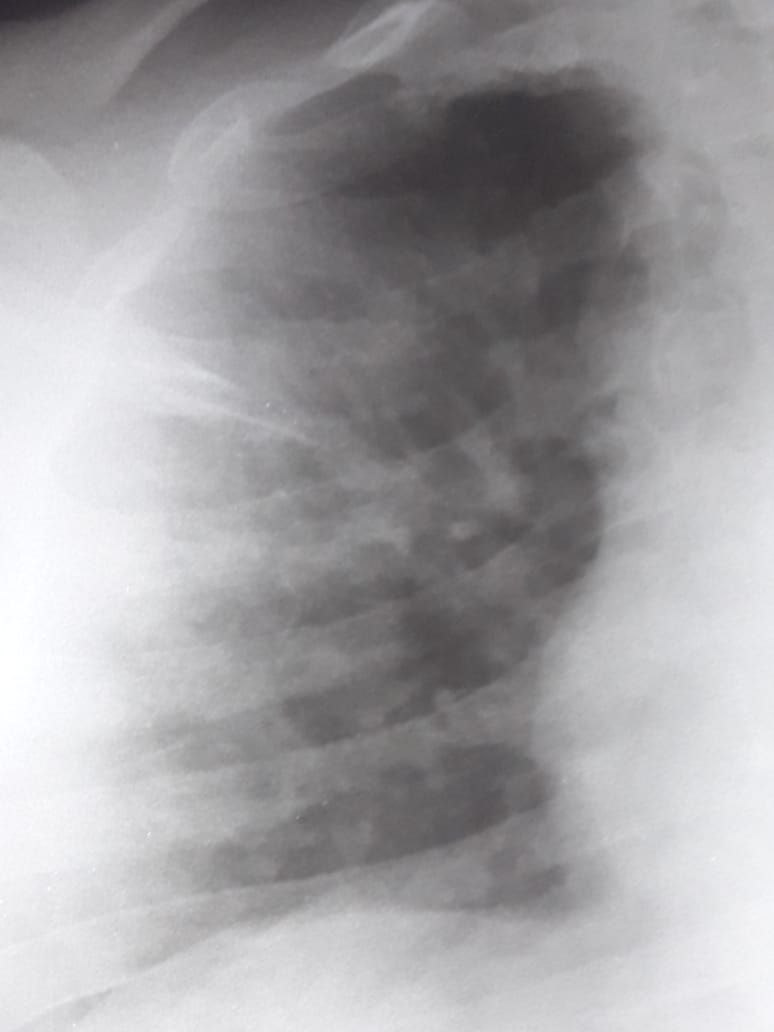

Добрый вечер коллеги. Что можете сказать по этому снимку?

Справа в 3 сегменте не похоже на инфильтрацию?

Гипертрофия левых отделов ❤️

Снимок какой-то древнегреческий

Походу он когда то переболел экссудативном плевритом

Можно поставить м о и

3 сегменте

Или фиброзные изменения в.д s 3

Справа

Влепи ему ещё хронический деформирующий бронхит

Это не рентгеновский диагноз. Ставится только по кт

Снимки без анамнеза🙃